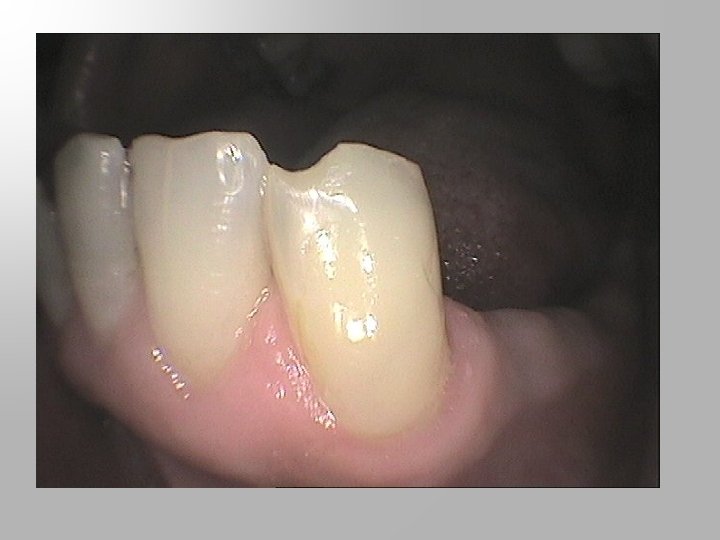

Unfavourable survey lines A high survey line on a tooth that is to be clasped is unfavourable because it requires the clasp to be placed too close to the occlusal surface and may create an occlusal interference (arrows). Even if an occlusal interference is not present, a high clasp arm is more noticeable to the patient and may interfere with mastication.

(1) A high survey line may also result in deformation of the clasp because, on insertion, the clasp is prevented from moving down the tooth by contact with the occlusal surface. If the patient persists in trying to seat the denture, the clasp is bent upwards rather than flexed outwards. (2) Shaping the enamel to lower the survey line will allow the clasp to be positioned further gingivally and it also provides a 'lead-in' during insertion, causing the clasp to flex outwards over the survey line as planned.